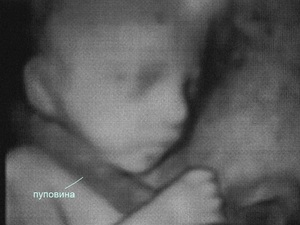

Что такое пуповина?

Чтобы глубже понять суть вопроса, важно сначала разобраться, что такое пуповина.

Это уникальная структура, которая соединяет организмы матери и ребенка. Через нее к плоду поступают все необходимые питательные вещества.

Процесс формирования пуповины начинается на третьей неделе беременности. Она состоит из соединительной ткани, пупочной вены и двух артерий. Внутри пуповины сосуды закручены спирально.

Пупочная вена отвечает за транспортировку артериальной крови от матери, насыщенной кислородом и питательными веществами, к организму ребенка. Артерии, в свою очередь, выводят от плода кровь, содержащую продукты обмена веществ.

Пуповина является временным органом. Она нужна плоду лишь до момента рождения. После появления ребенка на свет пуповину обрезают врачи.

В норме длина пуповины составляет от 40 до 60 см. Если же длина пупочного канатика превышает 70 см, это может привести к обвитию пуповиной вокруг шеи плода.